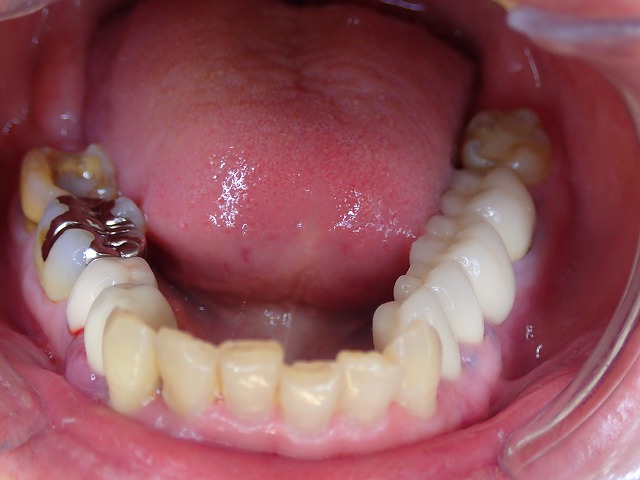

初診時画像

片側の仮歯はなし

クレージーな仮歯が入っています。

奥歯の修復物をすべて除去されて

仮歯にしたようですが

初診時 すでに復元が難しい状態まで、破壊されています。

これ仮歯??・

クレージーな仮歯

これが原因となり激しい炎症が起こります。

上の歯はほとんどが仮歯